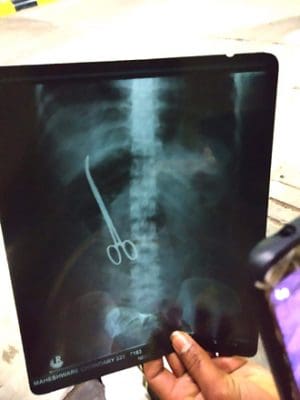

حیدرآباد : سرجن نے سرجری کے بعد قینچی مریض کے پیٹ میں ہی رکھ کر بھول گیا او رپیٹ کو سی دیا گیا ۔ بعد ازاں مریضہ کو اس بات